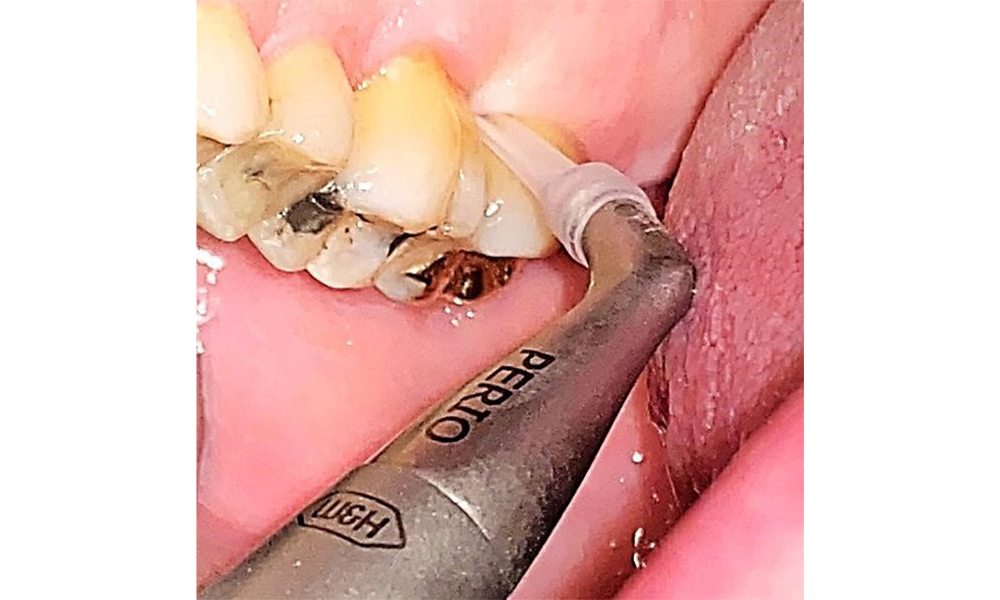

Use an ultrasonic tip to remove hard, mineralized plaque (Proxeo Ultra scaler with the Perio tip, W&H, shown here).

Fig. 9: Use an ultrasonic tip to remove hard, mineralized plaque (Proxeo Ultra scaler with the Perio tip, W&H, shown here). © Dr R. Krapf